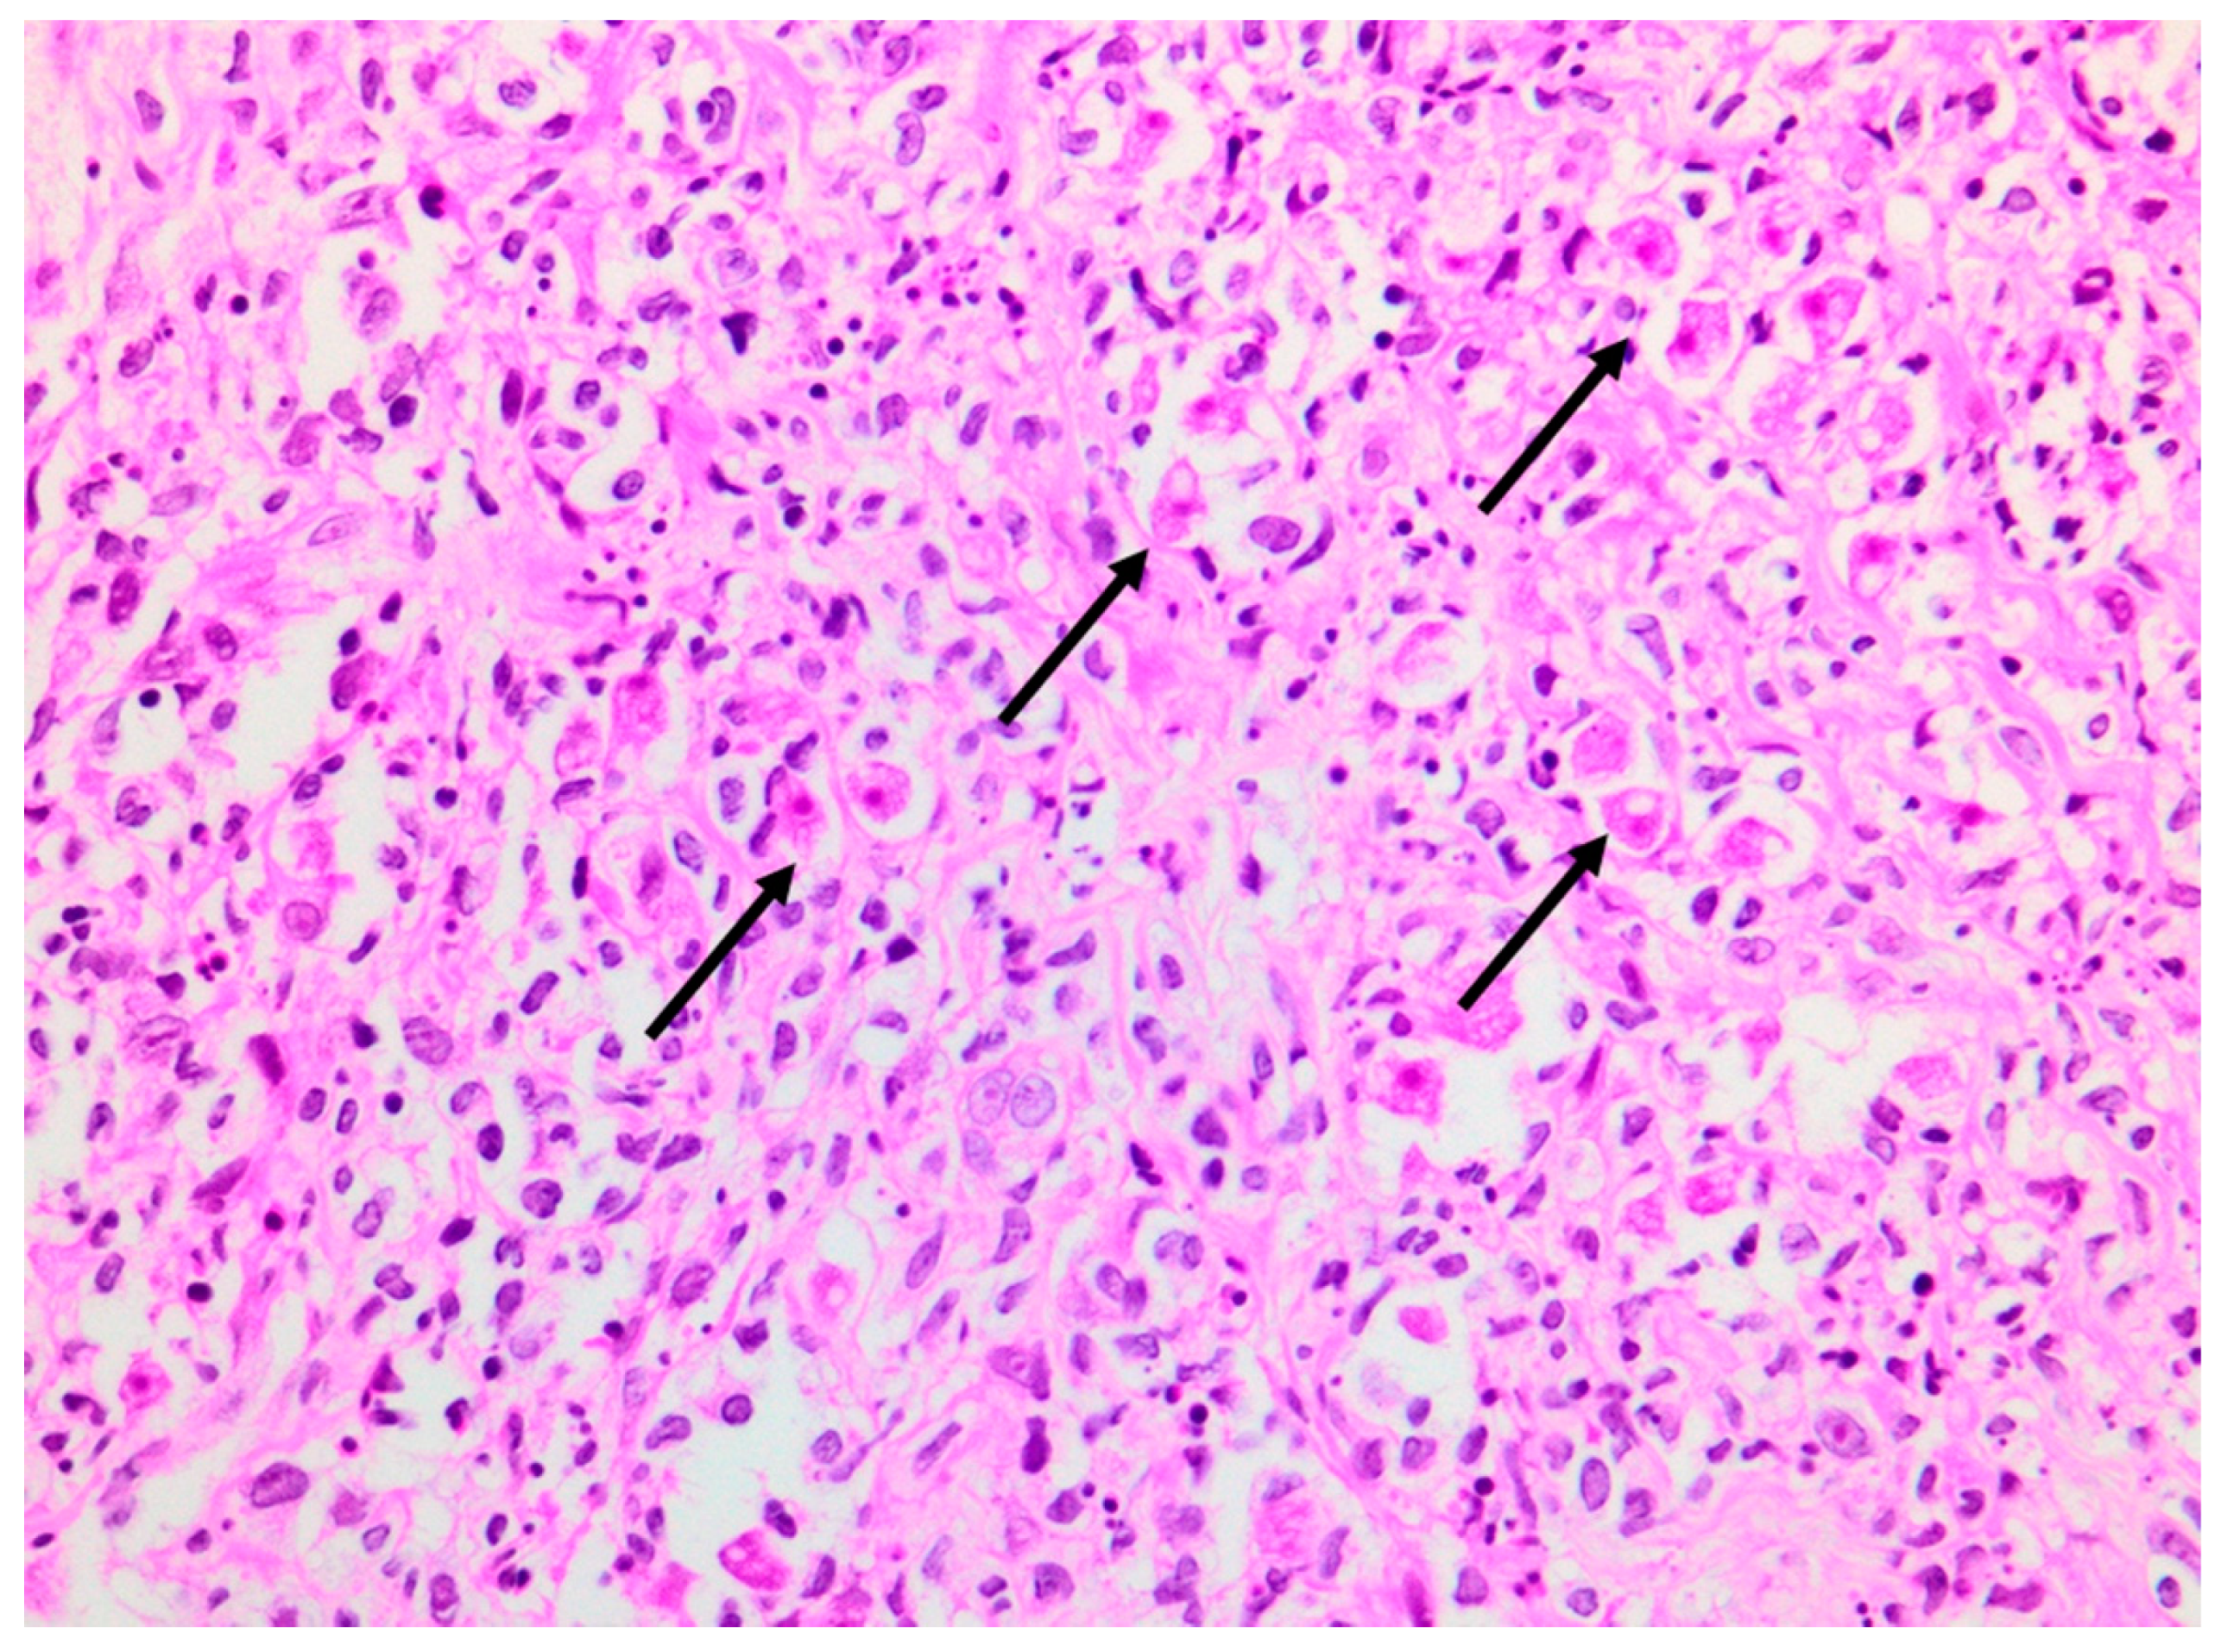

A deep skin punch biopsy was obtained from one of the lesions on the forearm, and submitted in 10% buffered formalin. The haematoxylin and eosin-stained sections revealed a polymorphous nodular deep dermal and subcutaneous inflammatory cell infiltrate comprising neutrophils, histiocytes, lymphocytes and eosinophils in response to conspicuous numbers of free-living amoebic organisms (Figure 5). Each round trophozoite was seen to possess a characteristic targetoid eosinophilic nucleus (Figure 6). Only rare, encysted forms were noted in the inflamed areas. Occasional subcutaneous vessels showed vasculitis. Erythrophagocytosis was conspicuously absent. There was no preponderance of histiocytic giant cells. The periodic acid-Schiff (PAS) stain was positive in some of the organisms, but the Grocott methenamine silver, TriPAS and Ziehl-Neelsen stains were negative. A diagnosis of cutaneous acanthamoebiasis was rendered, and the infectious diseases service was consulted. Further skin biopsies were sent to the national reference parasitology laboratory at the National Institute for Communicable Diseases (NICD). Cultures and PCR testing of the isolate performed at the NICD according to published methods [8,9] confirmed the presence of an Acanthamoeba species, with further 18s rRNA gene-sequencing identifying the isolate as a T4 strain, Acanthamoeba polyphaga (>99% identity with GenBank sequence accession no. MN153018.1).

Figure 5. Photomicrograph of skin punch biopsy showing numerous amoebic organisms (arrows) and a polymorphous background inflammatory infiltrate (haematoxylin and eosin, ×400).